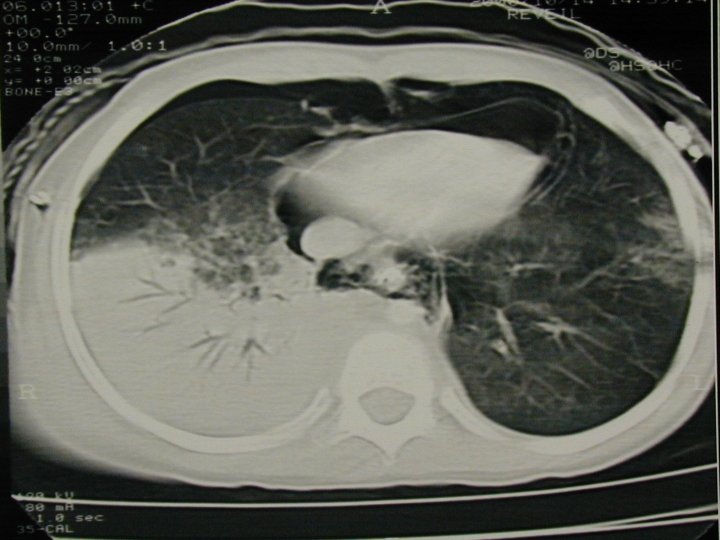

Lésions thoraciques - Peu ou pas de fractures pariétales - Contusions très fréquentes, diagnostic = TDM - Epanchements pleuraux rapidement compressifs - Atteinte cardiaque ou des gros vaisseaux exceptionnelles - Déplacement médiastinal facile -Plaies thoraciques anecdotiques -Retentissement +++